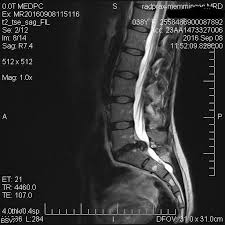

Wird ein Bandscheibenvorfall zwischen L5S1 früh diagnostiziert so ist eine rein konservative Therapie in den meisten Fällen vollkommen ausreichend. Die meisten Menschen mit einem Bandscheibenvorfall im Lendenwirbelbereich werden konservativ behandelt das heißt ohne Operation. Ich möchte mal im kurzen meinen Leidensgeschichte wiedergeben.

Eventuell kann auch eine gezielte Spritze an die Nervenwurzel zur lokalen Abschwellung sinnvoll sein. Wichtig ist dass eine Bettruhe und körperliche Schonung verhindert werden. Vor allem bei einem frischen oder wenig ausgeprägten Bandscheibenvorfall zwischen L5S1 können konservative Behandlungsmethoden beispielsweise spezielle Übungen und Physiotherapie hilfreich sein.